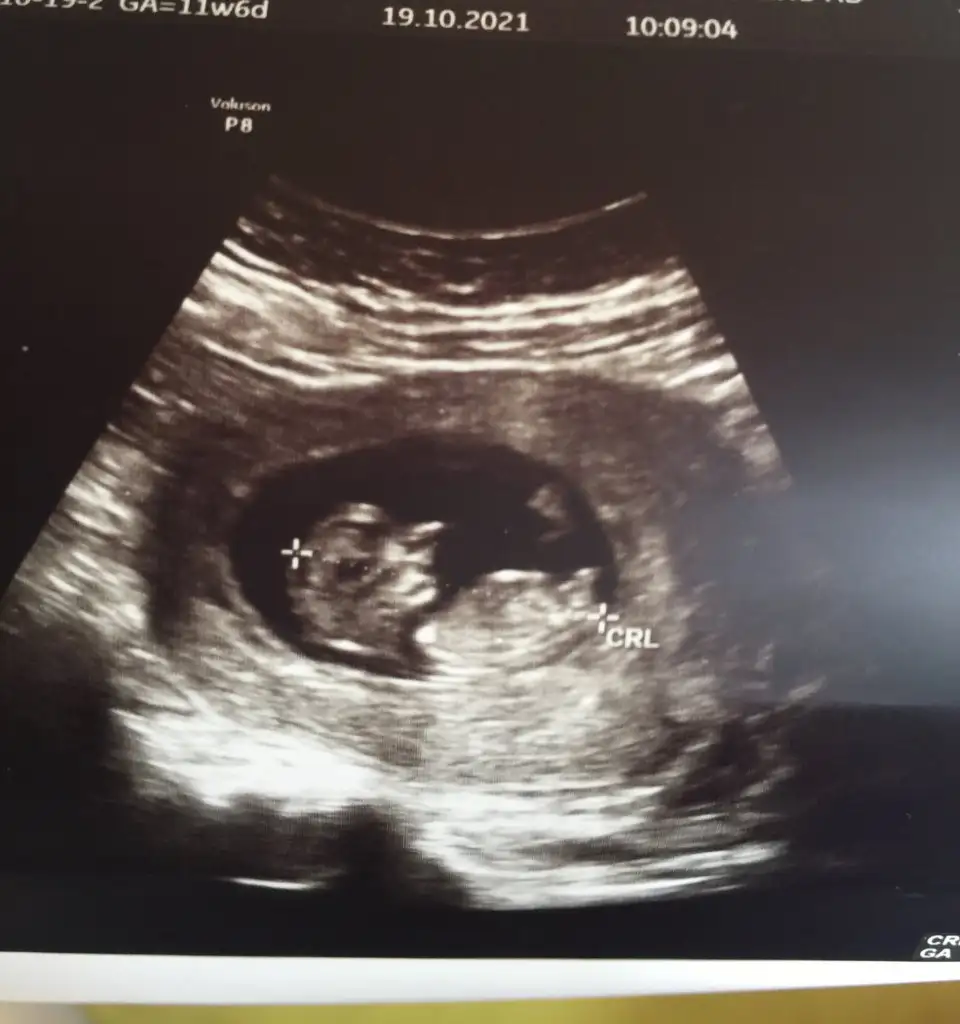

Emin olmadım sanki erkek gibiIkra meyra Merhaba, bu ultrason goruntuleri son adet tarihine gore 11+5, ultrason olcumune gore 12+3. Acaba cinsiyet icin bi yorum da bulunabilir misiniz ? Simdiden tesekkur ederim.

Doktor %70 kiz gibi ama daha erken onumuzdeki ay net belli olur dedi. Fakat prof dr oldugu icin yanilacagini sanmiyorum. Senin dr baya namini duydum sitede. Sen de emin olamamissin o zaman kız mi geliyor acabaEmin olmadım sanki erkek gibi

BakalımDoktor %70 kiz gibi ama daha erken onumuzdeki ay net belli olur dedi. Fakat prof dr oldugu icin yanilacagini sanmiyorum. Senin dr baya namini duydum sitede. Sen de emin olamamissin o zaman kız mi geliyor acaba